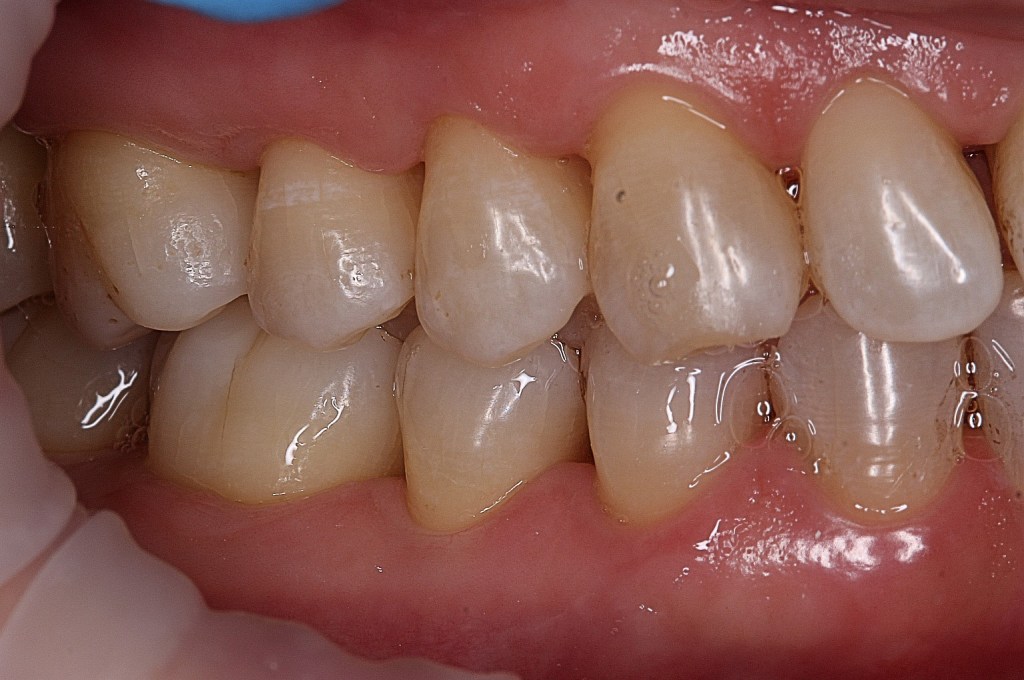

Atașez pozele unui pacient care până la vârsta de 44 ani nu a fost niciodată la dentist, cu reflex de vomă exagerat și igienă deficitară, speriat că i s-a propus extracția a peste 50% din dinți din cauza mobilității generalizate de gradul II și III. Am mers pe varianta clasică, debridare parodontală nechirurgicală, la microscop, cu anestezie locala în toate cadranele, realizată într-o singură ședință. Am administrat antibiotic pe cale generală și am urmărit respectarea indicațiilor de igienă prin controale lunare. Rezultatele la 6 luni vorbesc de la sine, acum putând să ne ocupam liniștiți de regenerarea defectelor osoase de la nivelul 21 22, de altfel singurii dinți care mai au mobilitate.

Iar retracția de la 31 s-a vindecat singură 🙂 Pentru că timpul e, uneori, cel mai bun tratament.